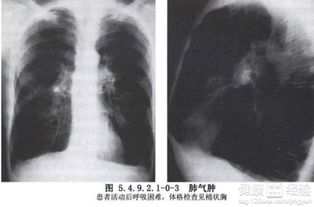

肺氣腫早期常無(wú)癥狀或僅感到氣促、胸悶、呼氣不暢。隨病情發(fā)展會(huì)感到進(jìn)行性呼吸困難,上樓時(shí)氣喘吁吁,心慌氣促,胸部呈圓桶狀。由于肺通氣和換氣功能障礙,常可造成缺氧、口唇、指甲有紫紺,可形成槌狀指,在寒冷季節(jié),特別是抵抗力和肺功能較差的老年病人,易合并肺部急性感染,加重病情,可發(fā)生呼吸衰竭。

肺氣腫是指終末細(xì)支氣管遠(yuǎn)端(呼吸細(xì)支氣管、肺泡管、肺泡囊和肺泡)的氣道彈性減退,過(guò)度膨脹、充氣和肺容積增大或同時(shí)伴有氣道壁破壞的病理狀態(tài)。按其發(fā)病原因肺氣腫有如下幾種類型:老年性肺氣腫,代償性肺氣腫,間質(zhì)性肺氣腫,灶性肺氣腫,旁間隔性肺氣腫,阻塞性肺氣腫。